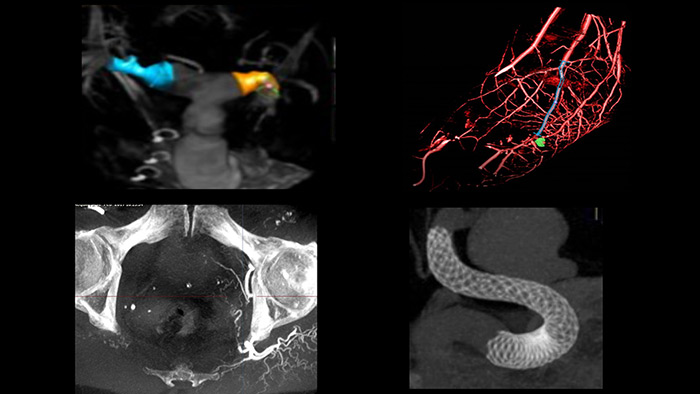

The SmartCT solution allows you to carry out advanced measurements and visualizations on the touch screen at table side to study the type and extent of disease with great detail. SmartCT 3D images can help reveal information not apparent in 2D or DSA images. This additional information may change diagnosis, treatment planning or treatment delivery, supporting better patient outcome.17-19

3D imaging can enhance diagnostic accuracy,20-22 improve patient outcomes23-25 and increase procedural efficiency in the interventional lab.17 Despite these advantages, it can still be considered difficult to perform by many users. To take the guesswork out of 3D acquisition, SmartCT provides step-by-step guidance and visual aids during acquisition to help any clinical user28 easily acquire 3D images.26 Guidance for room set-up, isocentering the system, as well as a suggested contrast injection based on literature27 and X-ray acquisition protocol is provided.

SmartCT provides CT-like 3D images in the interventional lab to support diagnosis, planning, treatment and follow-up for interventional radiology procedures. The 3D image data can be visualized, segmented and processed as a regular CT image with advanced 3D visualization and measurement tools. The ability to access CT-like imaging in the lab can free up the CT scanner for diagnostic purposes and thereby save time and prevent additional risk to patient.

SmartCT* provides CT-like images allowing you to carry out advanced measurements and visualizations on the touch screen at table side to study the type and extent of disease with great detail. SmartCT* 3D images can help reveal information not apparent in 2D or DSA images. This additional information may change diagnosis, treatment planning or treatment delivery, supporting better patient outcome.17-19